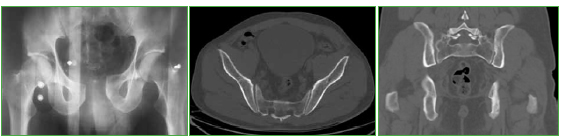

Flegmasia cerúlea dolens posquirúrgica inmediata en el tratamiento de una fractura de pelvis. Reporte de Caso